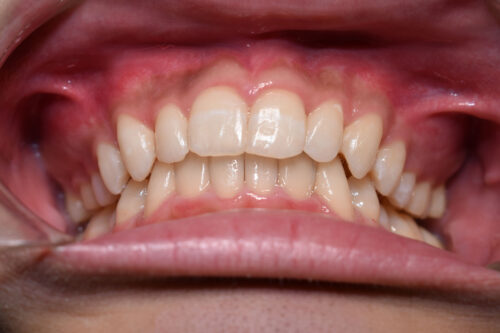

ワイヤー矯正治療 8か月後です。

全額矯正治療 88万円、

(装置を装着するまでは 1~2週ごと、その後3~4週に一回来院 (11回)

歯科矯正用アンカースクリュー(デュアル・トップオートスクリュー)上顎左右2本(25000円x2本分 提携医院にて)

ワイヤー期間 7か月,

マウスピース型カスタムメイド矯正歯科治療を用いた矯正歯科治療装置を利用した矯正治療 3か月間 22000円、

矯正矯正用アンカースクリュー(デュアル・トップオートスクリュー)上顎左右2本使用することで

下あごの オートローテーションを利用し

歯を抜かない矯正治療でも

口元が出っ歯にならずに

仕上げることができます。